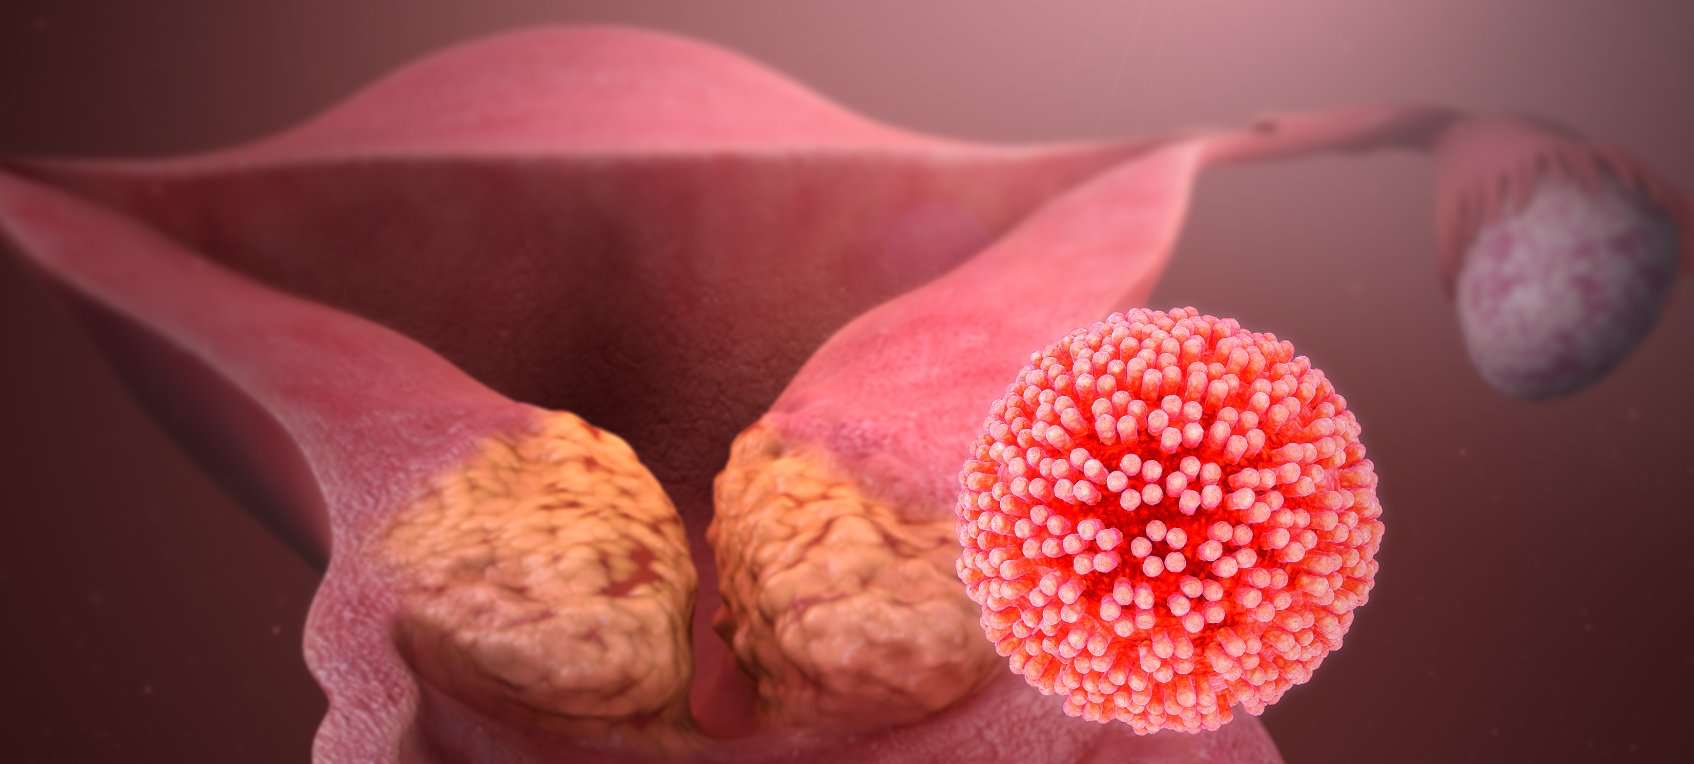

Фото раковой шишки на теле

Раковые шишки могут возникать не только на лице, но и на других частях тела. На фотографиях вы можете увидеть примеры раковых шишек на шее, руках, ногах и туловище. Обратите внимание на различные формы и размеры раковых шишек, а также на их внешний вид.